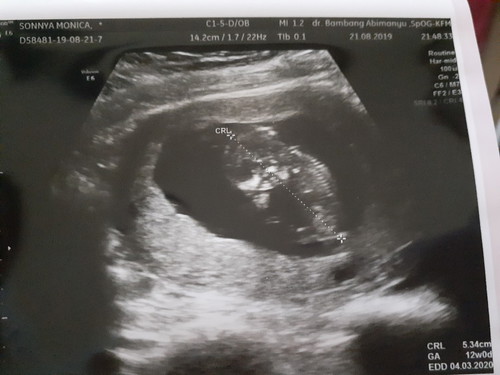

Mau crta sdkit nih bun², krna skg lagi hepi bgt ? Dlu kan sblm nikah aq emng haid nya ga teratur, kdg bisa sbulan ½, kdg bsa 2bln skli bru haid. Priksa kedokter ktanya krna hormon aja. Stlh mnikah pun msh sma haid ga tratur, pdhl aq kpengen bgt lgsg pnya baby, trnyta udh byk brusaha ga jdi² jg. Ngecek lah kdokter kndungan, dkter blg aq PCOS, sel telurnya byk tpi kecil², biasanya sel telur yg bsar bru bisa dbuahi & wktu itu suami ngecek jg hsilnya sprma krg, aq di kasih obat pnyubur & suami diterapi pke obt jg buat mmperbanyak sprma nya. Bln dpn ngecek lgi deh si suami hsilnya bgus dan sel telur q ada 1 yg bsar, dan bsoknya mulai dsruh dkter brhbgn 2hri skli. Kmi ikutin dong saran dkter siapa tau jdi? trnyta promil prtma gagal. Ya udh deh stop kdokter, mw alami aja ga pke obt² pnyubur, soalnya pke obt pnyubur kbnyakan ga baik bisa bkin kista(kta tmn² sih). Slma 6bln kmren haid jdi tratur tuh tglnya mleset² sdkit, ya brhbgn sprti biasa aja ga mkirin mw jdi apa ga tserah Tuhan aja, kita cm bsa brdoa&usaha. Ga nyangka aq bisa hmil?? pdhl udh pasrah aja sekasihnya Tuhan kpan. Puji Tuhan bgt skg udh jln 3bln, tdi bru usg dgr detak jntungnya mw mewek aq tahan(lebay sih hehe) pas djlan plg bru mewek? ga nyangka aja Tuhan ngasih pas disaat aq kmren ultah dan td bsa dgr dtak jntungnya stlh pnantian 3thun skg bru dkasih Tuhan ??❤